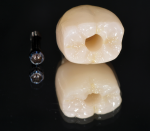

These difficulties can be overcome by using a screw-retained crown that offers an angulated screw channel (eg, the authors use the NobelProcera Full-Contour Zirconia Implant Crown; nobelbiocare.com) (Figure 7). The technology has allowed clinicians to overcome access issues by re-angulating the screw channel up to 25 degrees, thereby creating screw-retained restorations with favorable esthetics and ease of delivery in the posterior.

Coupled with this technology is the ability to mill the restoration from a highly esthetic, full-contour monolithic zirconia material that fulfills all of the functional and esthetic requirements of a posterior molar site (Figure 8 through Figure 10).